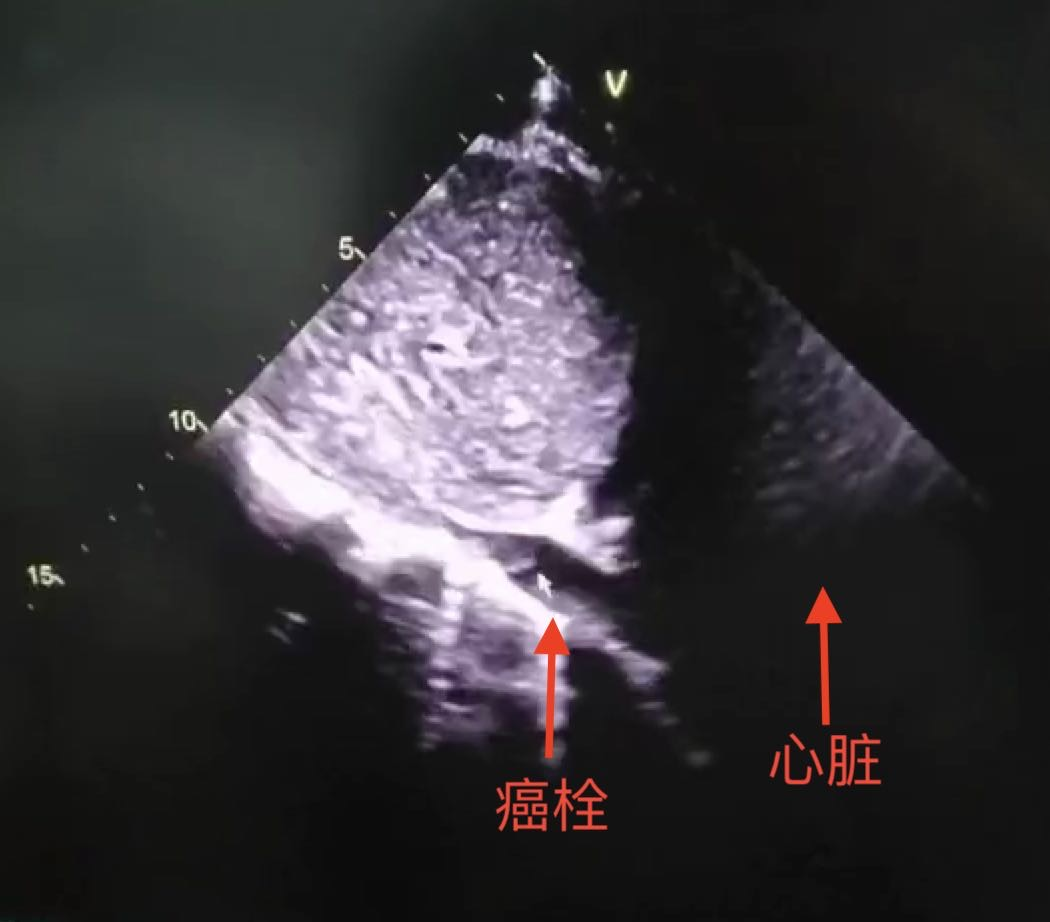

是典型的肾恶性肿瘤伴IV级癌栓

当地医生告诉陈先生,癌栓随时可能出现脱落,导致肺血管阻塞,引起猝死,十分危险!

入院后,薛学义教授团队对陈先生的肿瘤生长情况及肿瘤负荷进行全面地重新评估,发现其左肾恶性肿瘤体积巨大,同时合并破裂出血且已经伴有下腔静脉、左肾静脉、左睾丸静脉癌栓,且癌栓已经穿越膈肌蔓延至右心房入口处。

经过泌尿外科全科讨论后诊断,陈先生诊断为左肾恶性肿瘤伴有IV级癌栓,虽然手术风险很大,但手术仍是最佳治疗手段,如果能够完整切除肿瘤并将癌栓取出,患者仍可能获得长期存活,生活质量明显提高。